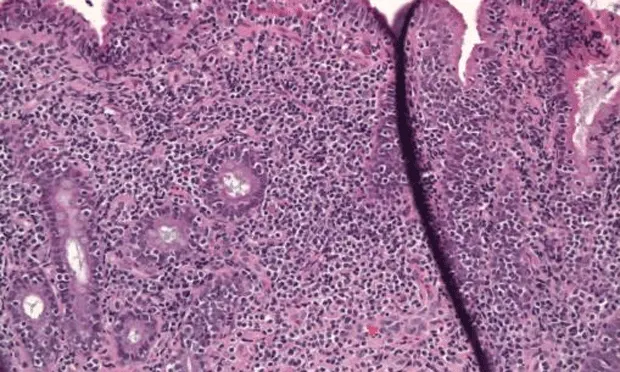

• IBD is associated with infiltration of the gastrointestinal mucosa with inflammatory cells (Figure 1), which is speculated to occur because of unusual stimulation of a normal enteric immune system or the usual stimulation of a hyperreactive immune system.7